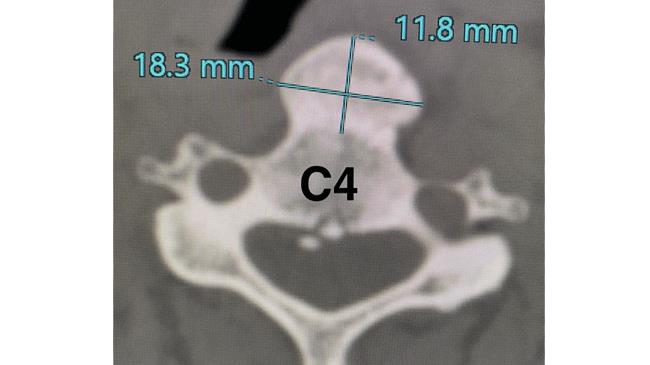

Sau thăm khám và kết quả chụp Citi 160 lát cột sống cổ cho thấy bệnh nhân có khối vôi hóa dây chằng dọc trước lớn liên tục dọc theo mặt trước thân sống C3-C6.

Các bác sĩ chuyên khoa Ngoại Thần Kinh ghi nhận chẩn đoán bệnh nhân bị vôi hoá dây chằng dọc trước gây hẹp thực quản. Đây cũng là một tình trạng bệnh khá hiếm gặp và khó phát hiện với những biểu hiện bệnh không đặc thù.

Cột sống cổ có 7 đốt sống xếp chồng lên nhau, từ C1 – C7. Trong đó gai mọc ở đốt sống cổ C4 C5 C6 là phổ biến nhất.